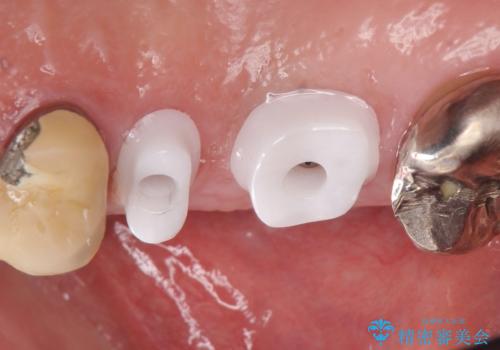

右上の567ブリッジを外したところ、右上5は歯根破折により保存不可能だったため、右上56部にインプラントを埋入し欠損補綴を行いました。

- オールセラミッククラウン…¥100,000×2、仮歯…¥10,000×2、歯槽堤保存術…¥100,000、インプラント(ストローマン)…¥200,000×2、カスタムアバット…¥100,000×2費用は治療当時の料金となります

今回用いたオールセラミッククラウンはジルコニアフレームという白い素材の上にセラミックを盛っているため、審美性が非常に高いのが特徴です。

また、ジルコニアは人工ダイヤモンドの材料にも使われているほど高い強度を持っており、そのためオールセラミッククラウンは審美性だけでなく、奥歯やブリッジの補綴も可能とするクラウンです。

カスタムアバットメントは患者様それぞれの歯茎に合わせて製作されたオーダーメイドのアバットメントです。

既製のアバットメントに比べ適合がよく、高い清掃性を誇ります。